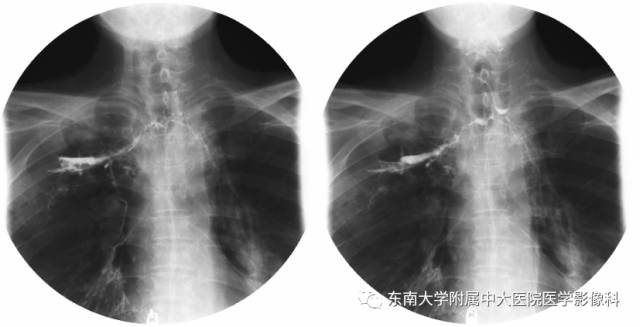

男,60岁,因“食管癌术后5年余,进食呛咳10天”入院。

食管造影